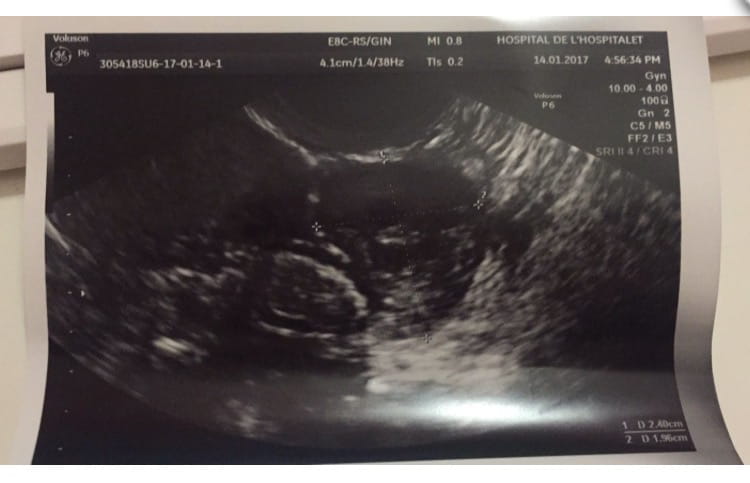

Que partes son estas ecos?

Que parte son estas ecografias? Son del utero, del ovario? De que? Jeje gracias

Los anexos no se ven claramente pero en la primera y la tercera han intentado enfocarlas... las otras son de útero.

Muchas gracias por responder!! Por cierto a la otra te refieres con la del medio y la que sale una imagen sola no? Esque a mi me dijeron que eso era un ovario pero yo no le veo pinta de ovario... Pd: que es lo que hay en mi "utero"?